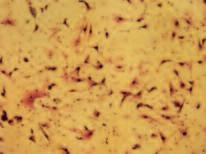

Immagine al microscopio di cellule leucemiche. Le sfere rosse del pacmen rappresentano gli enzimi collagenasi.

La foto nella pagina a fianco mostra una sezione trasversale al microscopio del fegato di un paziente con ‘leucemia linfatica’. Ciascuno dei piccoli puntini viola nella foto è un globulo bianco (in questo caso linfocita) che ha invaso il tessuto del fegato (aree rosa).

Considerando l’enorme quantità di questi puntini viola e il numero di enzimi che assimilano il collagene che ciascuno produce, è facile prevedere l’ingente distruzione del tessuto connettivo e il danno apportato all’organo da questo tipo di cancro.

Immagine al microscopio della leucemia linfatica

Globuli bianchi affetti di cancro (linfociti) invadono il fegato L’enorme quantità di collagenasi prodotte da queste cellule distruggono l’organo e causano insufficienza epatica.